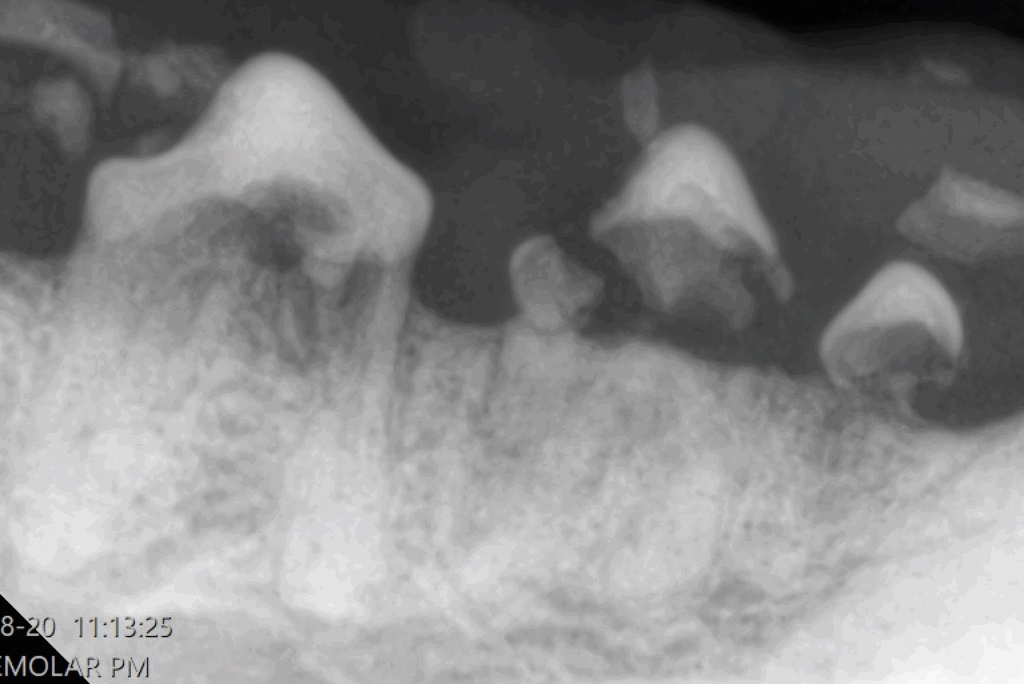

歯冠吸収病巣は、歯の表面(エナメル質・象牙質)が破壊され、徐々に歯が溶けていく病気です。

外からは正常に見えても、レントゲンで初めて異常が確認されるケースが多くあります。

| ステージ 2 | 吸収が象牙質まで進行。ただし歯髄(神経)までは到達していない。 | 外から見ても変化は分かりにくいが、冷たい物や噛むことへの反応が出ることがある。治療介入を検討。 |

| ステージ 3 | 吸収が歯髄に達する。内部の神経や血管も影響を受けている。 | 痛みが明確になる。食欲低下や咀嚼の偏りが見られることも。通常は抜歯対象。 |